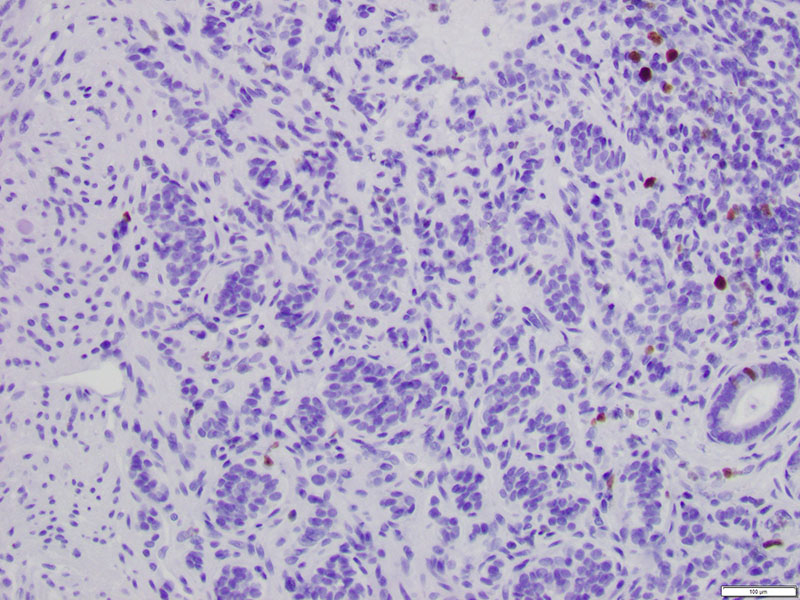

The patient is sent for an esophagogastroduodenoscopy (EGD), which reveals a 2 c.m. polyp in the third segment of the duodenum. Biopsy confirms duodenal adenoma, for which the patient elects to undergo an EGD with endoscopic mucosal resection (EMR).Microscopic examination demonstrates duodenal mucosa with low-grade epithelial dysplasia overlying foci of bland, monotonous cells with scant cytoplasm (Figures 1 & 2). The cells are arranged in nests and trabeculae that infiltrate into the superficial muscularis mucosae (Figure 3). Immunohistochemistry shows positive staining for synaptophysin (Figure 4) and chromogranin (Figure 5), as well as a Ki-67 labeling index < 1% (Figure 6).